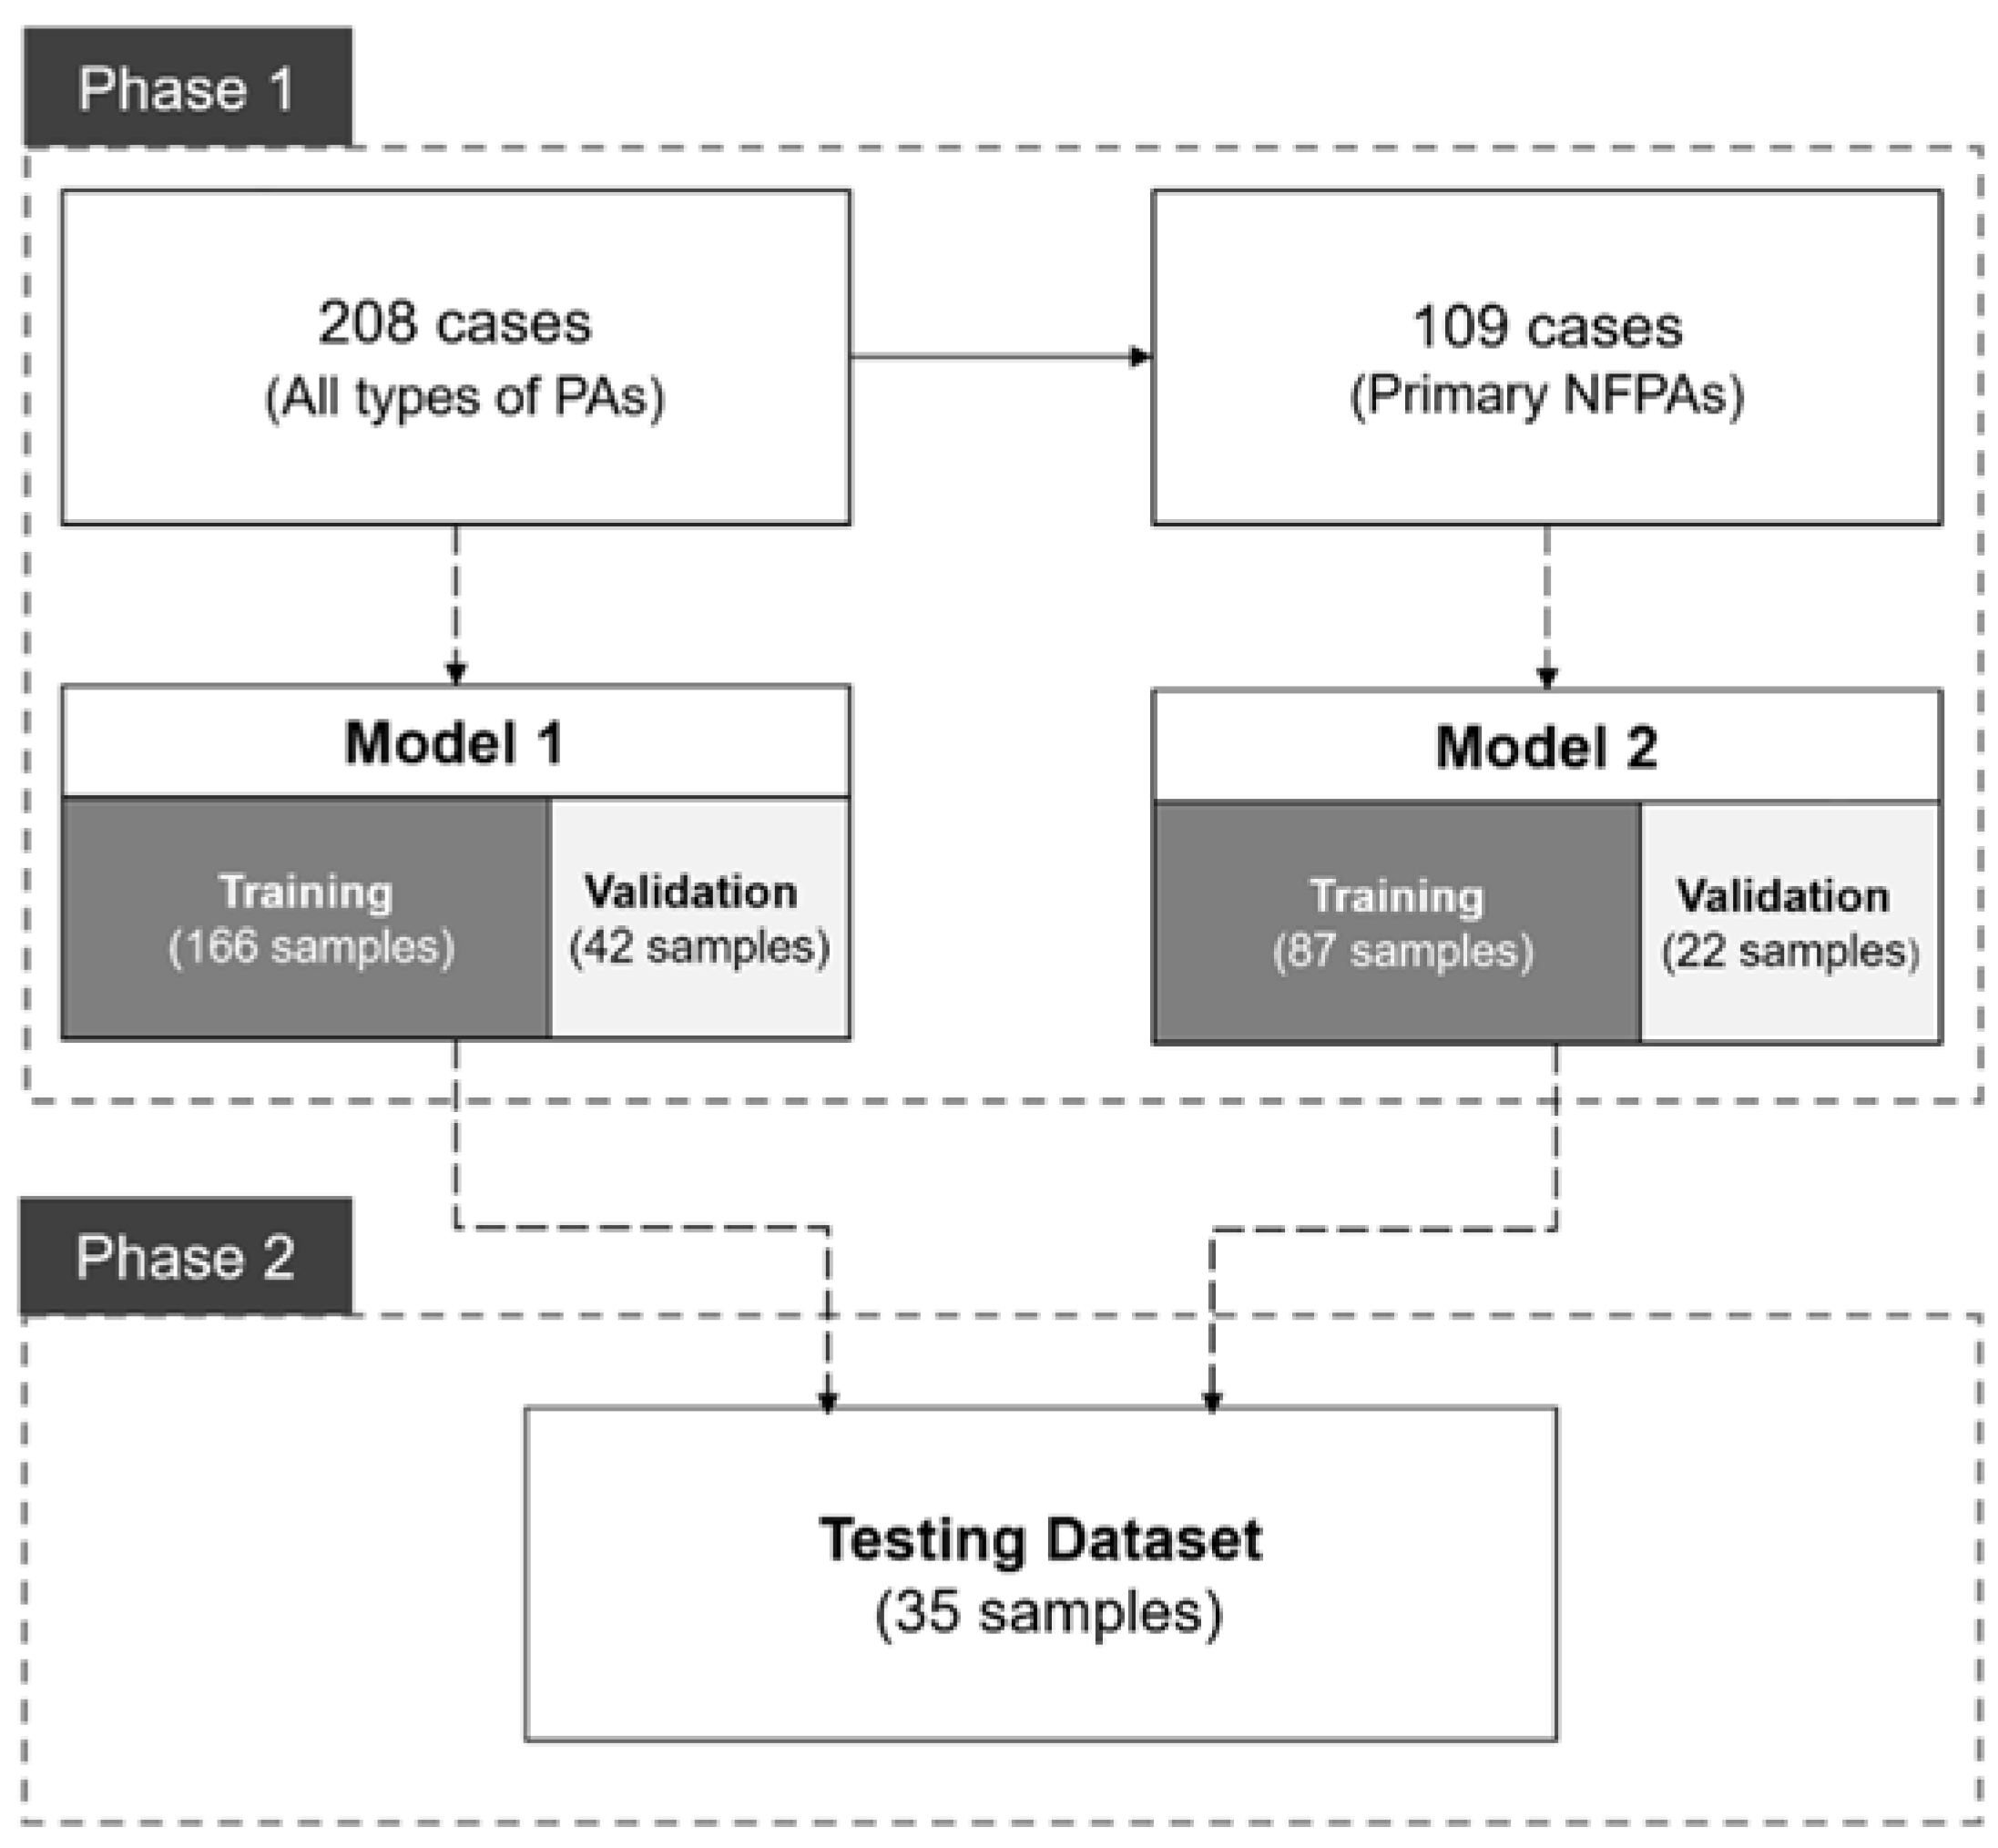

2.5. Study Design

3.2. Model Training and Evaluation

3.3. Model Performance in the Validation Dataset